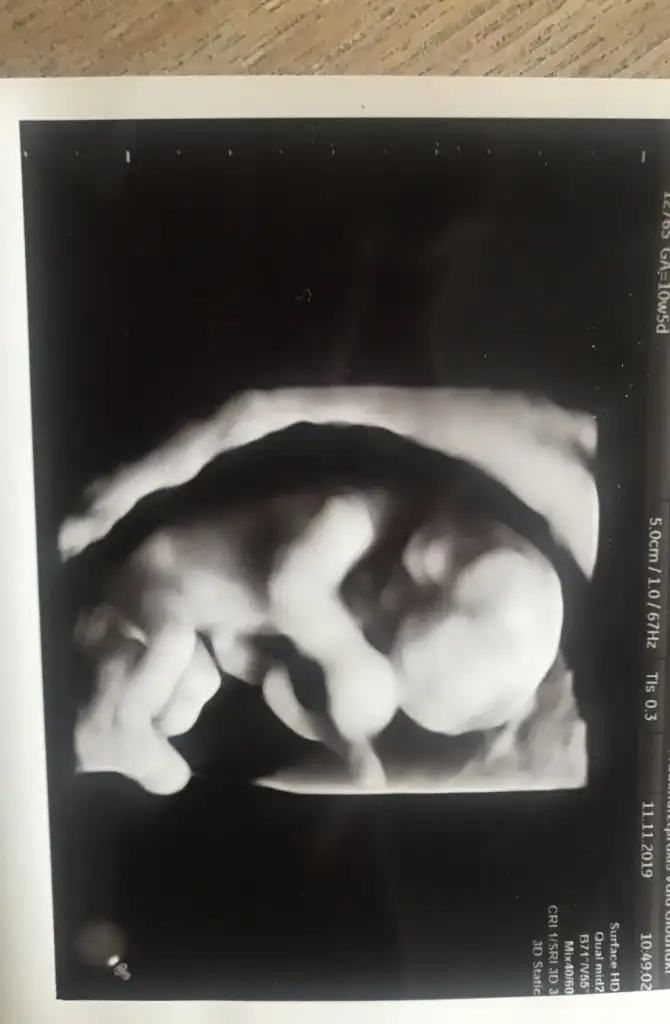

Banada erkek demiştiniz hatta baya net erkek demiştiniz kız diyince doktor şaşırmıştınız bnde çok şaşırmıştım tabi çünkü baya umutlanmıştım 2 kızım var doğal olarak değişik olsun istemiştim tabiki Rabbim in dediği olur ama hala erkek hissediyorum ayrıntılıda pozisyonu tersti cinsiyeti gözükmüyor demişti perinatolog ama 2 doktor kız gibi biride düşük kalitede bir cihazda kız demişti sonra rüyamda bebeğimin isminin koyulduğunu gördüm mavi nüfus kağıdında Ali arif yazıyordu bilemiyorum hala erkek hissediyorum pembe kıyafetleri almama rağmen

az kaldı sonucu görmeye herşey den önce Rabbim sağlıklı ve hayırlı evlatlar nasip etsin bizlere